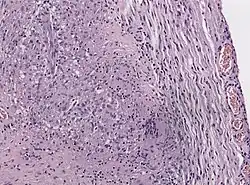

| Neuro-ophthalmologic examination showing ophthalmoplegia in a patient with Tolosa–Hunt syndrome, prior to treatment. The central image represents forward gaze, and each image around it represents gaze in that direction (for example, in the upper left image, the patient looks up and right; the left eye cannot accomplish this movement). The examination shows ptosis of the left eyelid, exotropia (outward deviation) of the primary gaze of the left eye, and paresis (weakness) of the left third, fourth and sixth cranial nerves. | |